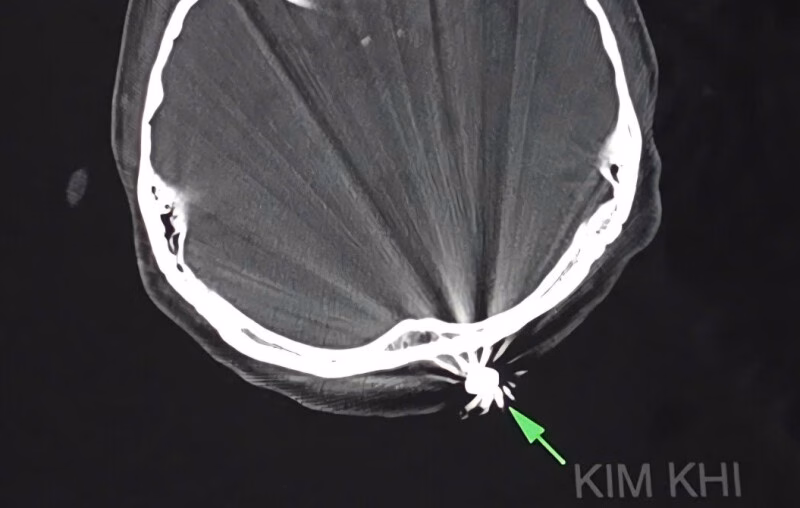

Ngay sau khi bị thương, chị T. được đưa đến bệnh viện trong tình trạng đau đầu, với một vết thương nhỏ khoảng 1cm ở vùng chẩm đã cầm máu. Các bác sĩ tại Khoa Ngoại thần kinh của bệnh viện đã nhanh chóng tiến hành phẫu thuật để lấy dị vật và xử trí tổn thương. Để lấy ra dị vật kim khí là đầu đạn có kích thước 0,5×0,3cm, các bác sĩ đã phải mở rộng vết mổ lên khoảng 3cm.

Ca phẫu thuật diễn ra trong khoảng 45 phút và kết thúc trong thành công. Điều đáng chú ý trong trường hợp này là viên đạn chỉ xuyên qua lớp da và chạm nhẹ vào xương chẩm, không gây ra bất kỳ tổn thương nào đến não và các cấu trúc lân cận. Hiện tại, bệnh nhân tỉnh táo, tiếp xúc tốt, vết mổ khô và không ghi nhận bất kỳ triệu chứng thần kinh khu trú nào.